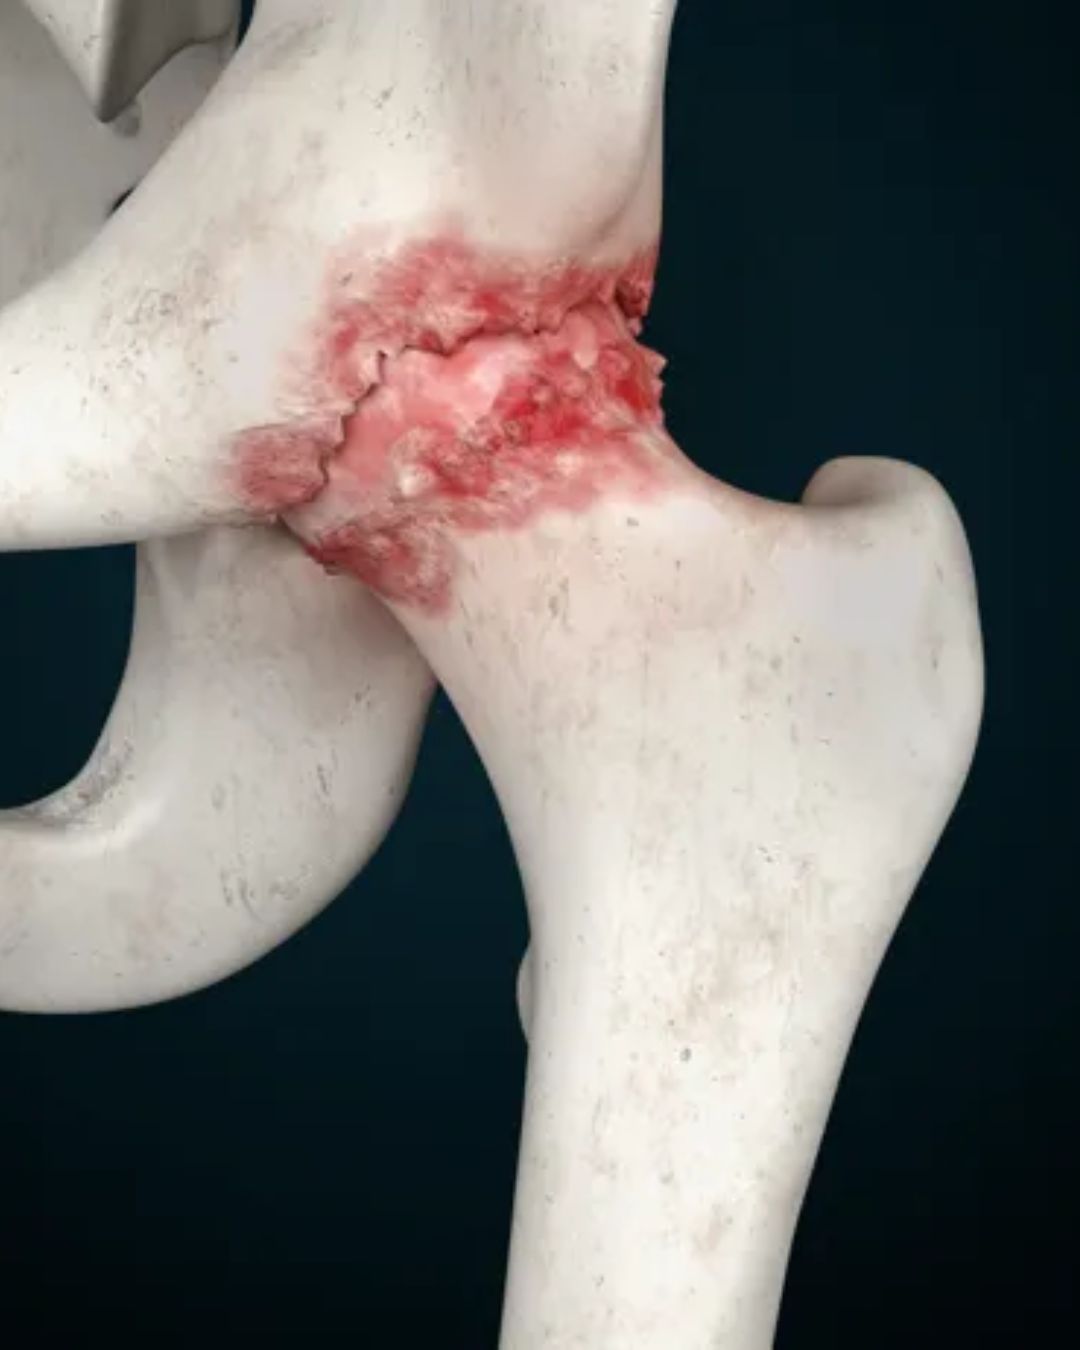

Osteoarthritis of the hip

Rheumatoid arthritis

Hip fracture (especially in elderly patients)

Severe hip stiffness and deformity